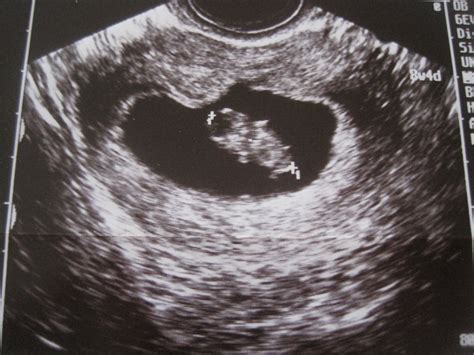

Dieta per il primo trimestre di gravidanza. Avviene, infatti, la nidazione nell'utero dell'ovulo fecondato e il feto inizia la sua prima fase di vita. Calendario della gravidanza il primo trimestre. Giovane età, obesità, fumo e il fatto che si tratti della prima gravidanza sono tutti fattori di rischio per questo problema, che in genere tende a ripresentarsi anche alle gravidanze successive. I primi tre mesi della gravidanza sono un periodo importante in cui il corpo e la mente della donna cominciano ad adattarsi ai cambiamenti in arrivo, non sempre semplici da gestire.